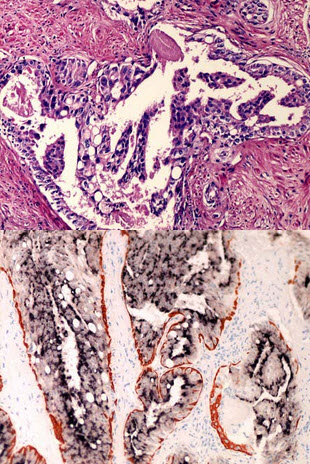

男,55岁,排尿不畅一年,进行性加重二月余。肛诊前列腺肥大。行前列腺摘除,大体见前列腺肿块灰白色,质地中等偏硬。镜下如图所示,腺上皮簇状、微乳头状,细胞异型并可见小核仁,鸡尾酒法染色如图。应诊断为()

[单选题]男性,58岁,排尿不畅半年余,检查前列腺肿大,穿刺显微镜下未见癌。行前列腺切除术,术后病理检查见部分腺管细胞层次增多(如图),用鸡尾酒法染色(如图)。应诊断为()A . 前列腺良性增生B . 前列腺基底细胞增生C . 低级别上皮内瘤变D . 高级别上皮内瘤变E . 导管内癌